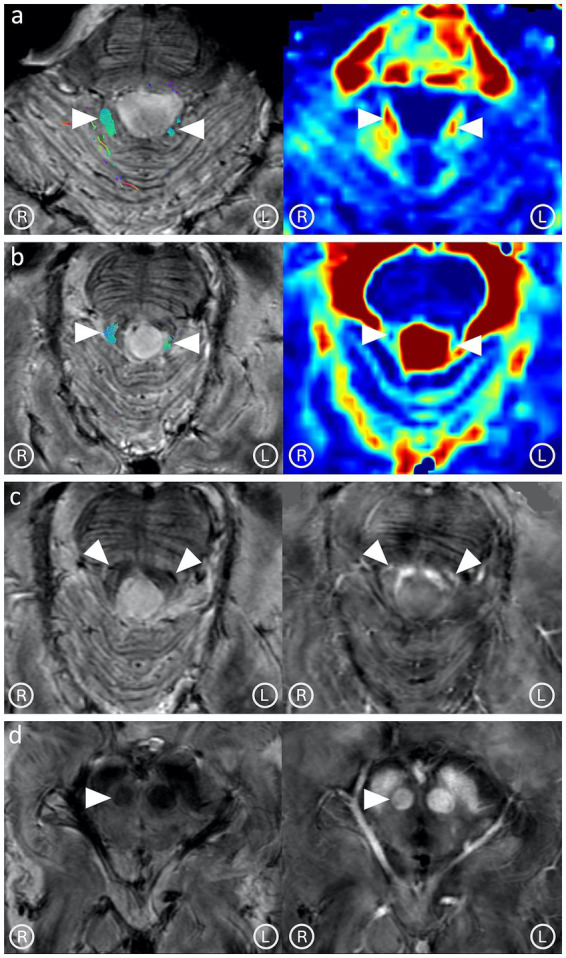

背景和目的:一名50岁的患者出现共济失调、眼球震颤和腭震颤。常规磁共振成像(MRI)显示下橄榄核增大,t2加权图像呈高信号,提示肥厚性橄榄核变性(HOD)。患者既往病史报告质子治疗脑神经神经鞘瘤。在这里,我们的目的是利用先进的超高场(7 T) MRI方案研究构成齿状-红宝石-橄榄通路(Guillain-Mollaret三角)的束和核的潜在改变。材料和方法:患者行7 T-MRI脑部检查,包括多回声梯度-回声序列定量敏感性成像和弥散张量成像(DTI)。对DTI数据集进行了详细阐述,用于轨迹成像和张量度量的计算。结果:7 T-MRI可以描绘脑干束和组成格林-莫拉雷三角的核。对这些结构的定性和定量分析均显示右侧红核和双侧齿状丘脑束受损。这些发现与HOD的病理生理学一致,并在后续的MRI中得到证实。讨论:本研究强调了7 T-MRI描述和研究脑干亚结构(如束和核)的能力。据我们所知,这是第一个描述构成格林-莫拉雷三角的所有束并直接记录它们在HOD中的变化的研究。

Background and objectives: A 50-year-old patient developed ataxia, nystagmus, and palatal tremor. Conventional magnetic resonance imaging (MRI) revealed inferior olivary nuclei enlargement and hyperintensity in T2-weighted images, indicating hypertrophic olivary degeneration (HOD). The patient's past medical history reported proton therapy for an VIII cranial nerve Schwannoma. Here, we aimed to investigate the potential alterations involving tracts and nuclei composing the dentato-rubro-olivary pathway (Guillain-Mollaret triangle) using an advanced ultra-high field (7 T) MRI protocol.

Materials and methods: The patient underwent a 7 T-MRI brain exam, including a multi-echo gradient-echo sequence for quantitative susceptibility mapping and diffusion tensor imaging (DTI). The DTI dataset was elaborated for tractography and computation of tensor metrics.

Results: 7 T-MRI allowed the depiction of the brainstem tracts and nuclei composing the Guillain-Mollaret triangle. Both qualitative and quantitative analyses of these structures demonstrated damage to the right red nucleus and the dentato-rubral tracts bilaterally. These findings are consistent with the pathophysiology of HOD and were confirmed in a follow-up MRI.

Discussion: This study highlights the capability of 7 T-MRI to depict and investigate brainstem substructures such as tracts and nuclei. To the best of our knowledge, this is the first study to depict all tracts composing the Guillain-Mollaret triangle and directly document their alterations in HOD.